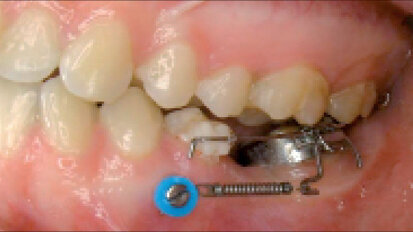

Miniimplantáty: ústřední bod ortodontické praxe. Část I. ze VI: Základy a historie kotvení – výběr šroubů

S ohledem na nepřeberné množství publikací, kurzů a reklamních materiálů na dané téma se může ...